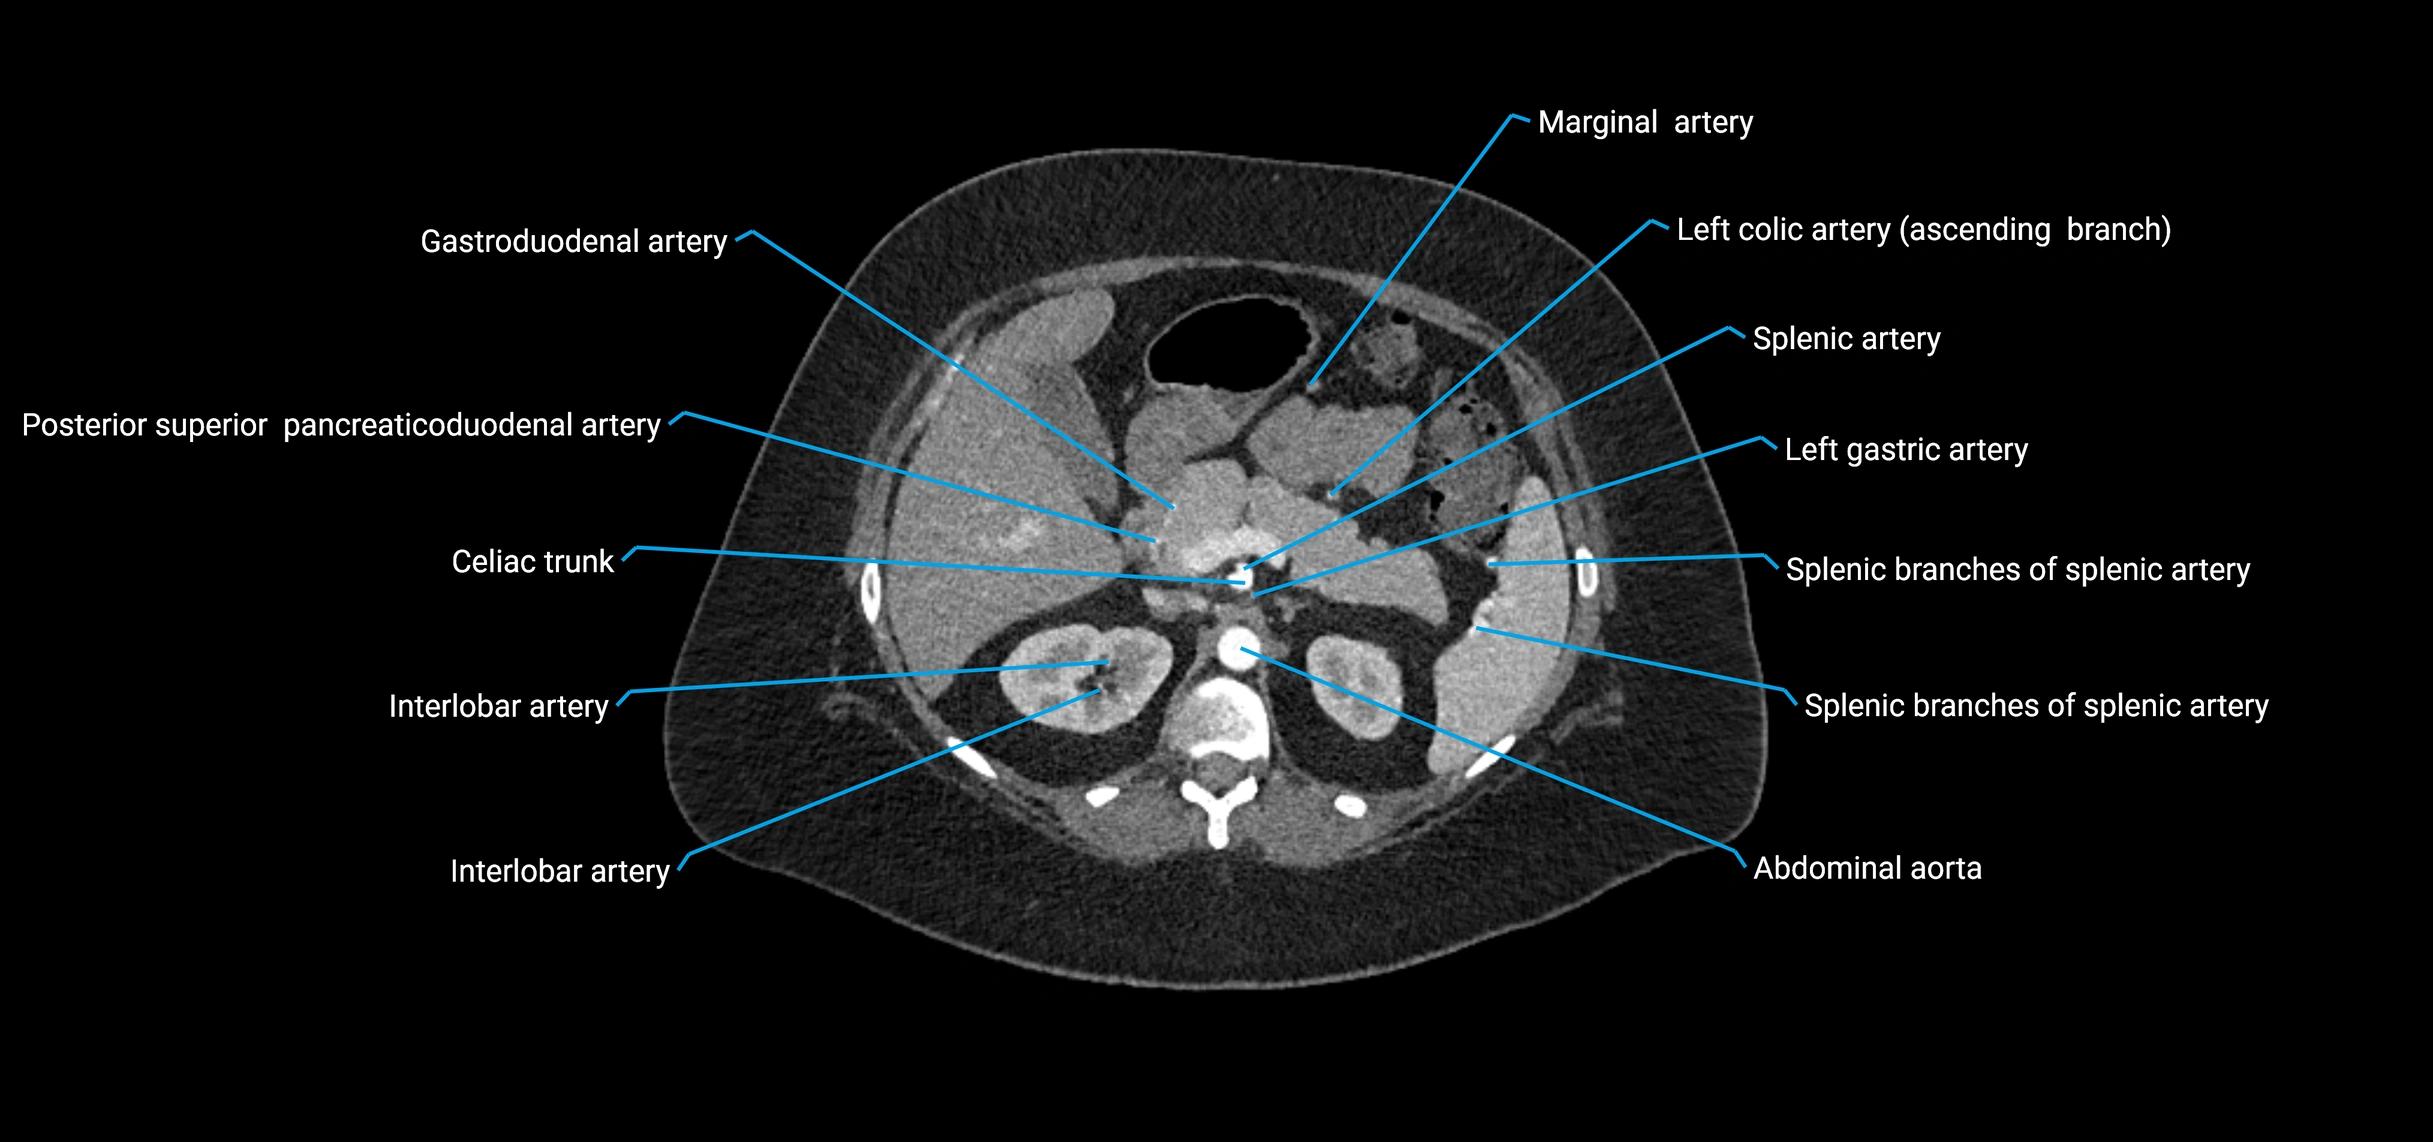

Contrast-enhanced CT (CTA):

• Gold standard for abdominal aortic imaging

• Provides excellent detail of lumen, wall, aneurysm, thrombus, and branch vessels

• Multiplanar and 3D reconstructions help in aneurysm measurement, stent graft planning, and dissection evaluation